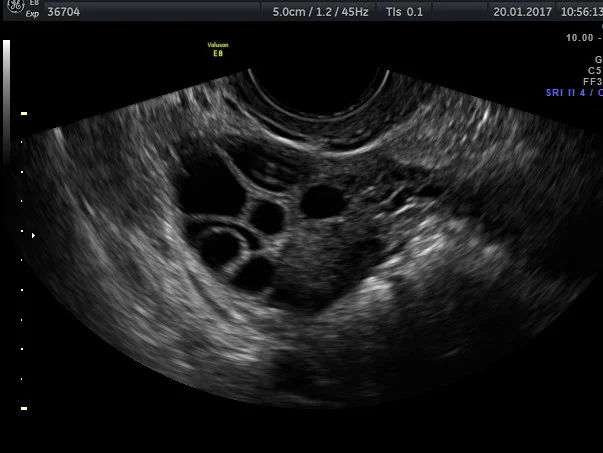

Polycystic ovarian

The ovaries produce hormones which control the uterus. Some conditions can alter the hormonal production and stop the ovaries producing an egg (ovulation) each month. An example of this is polycystic ovarian syndrome

During the reproductive years, the ovaries are continually going through the cycle of egg production. This involves the formation and resolution of a cyst. Sometimes this process does not function perfectly and the cyst may become very large.